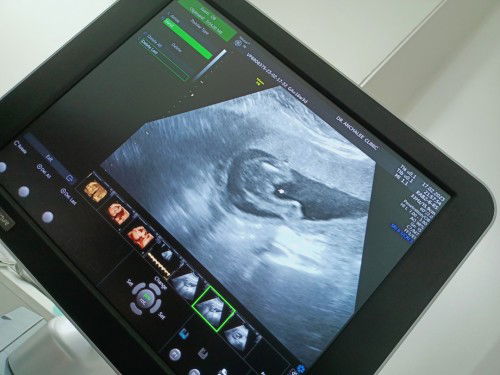

หมอบอก มันเล็กมากมากๆ 16 วีค รูปที่2เป่นสายสะดือได้ไหมค้ะ หมอบอกดูไม่ชัด บางทีก้อเรียบ บางทีเหมือนมี เเต่เล็กมากๆ#ขอบคุณล่วงหน้านะคะ #ขอบคุณสำหรับคำตอบค่ะ #ขอคำแนะนำหน่อยค่ะ

มีสิทธิ์ เป็นสายสะดือไหม 16 วีค ถ้าผู้ชาย เห็นชัดแค่ไหนค้ะ#ขอบคุณล่วงหน้านะคะ #ขอบคุณสำหรับคำตอบค่ะ #คุณแม่ๆช่วยแนะนำหน่อยค่ะ